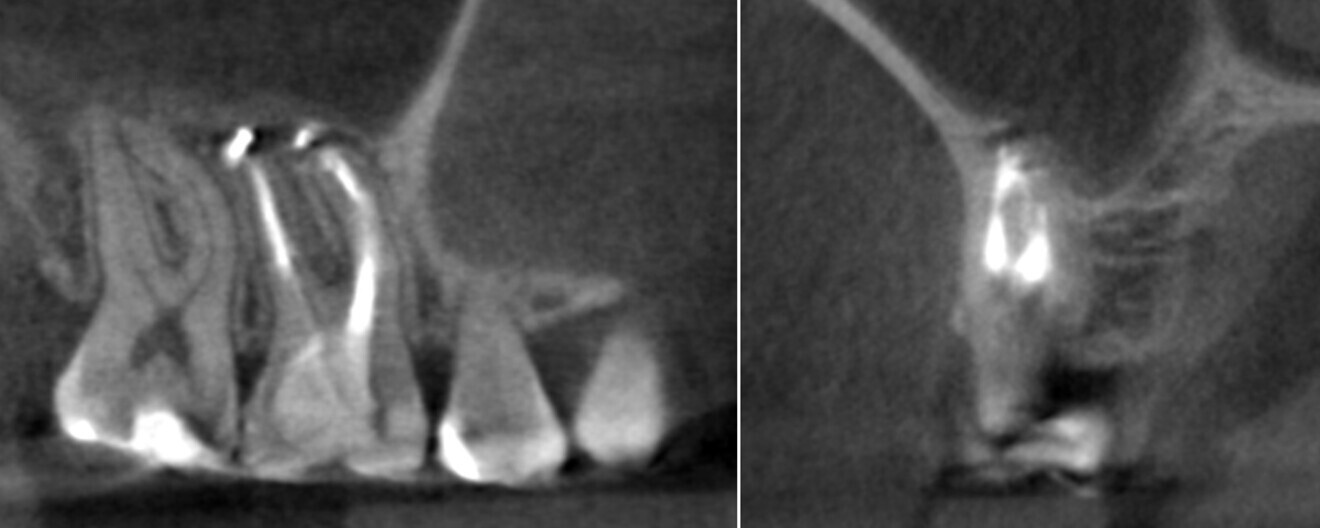

A 28-year-old female patient was referred to Dr Karaś’s office because the previous dentist was not able to locate the orifice of the second mesiobuccal (MB2) canal in tooth #16. Owing to her medical history, endodontic treatment was performed, the tooth being symptomatic. A CBCT scan was performed in order to examine the mesial root and create a treatment plan. The shape of the root and the widening of the periodontal ligament indicated a separate path and apical foramen of an MB2 canal. Also, the slice showing the palatal part of the MB root revealed a small path, suggesting the presence of an MB2 canal. There were also visible signs of inflammation around the apices of the MB and distobuccal (DB) root and in the membrane of the maxillary sinus (Fig. 1).

During the consultation appointment, a CBCT scan was performed. It revealed a small osteolytic lesion around the mesial root, suggesting the possibility of achieving patency in the root canals in the mesial root. Around the distal root, there were no signs of the lesion, which indicated that the mesial root was the cause of the symptoms. The radiographic examination also revealed a broken lentulo in the MB canal (Fig. 16).

Figs. 16 a & b